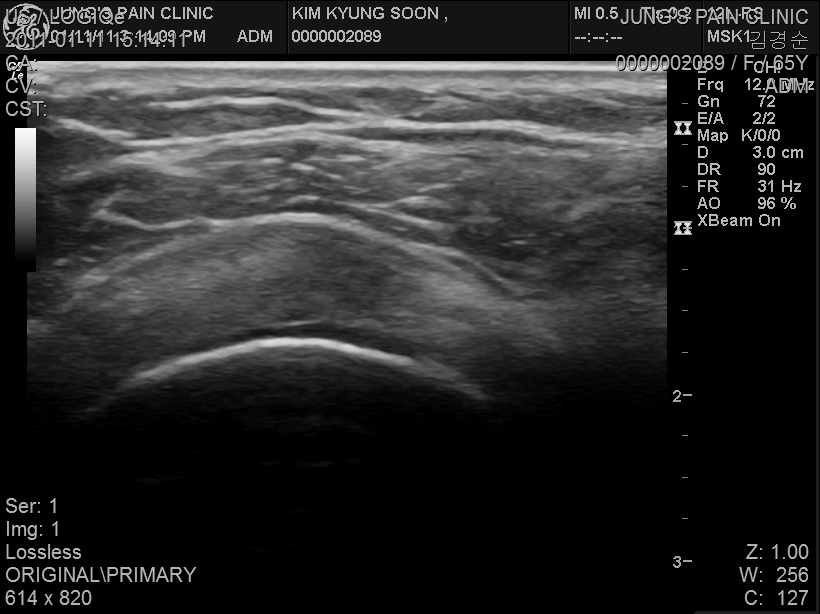

supraspinatus tendinosis

Rt shoulder pain